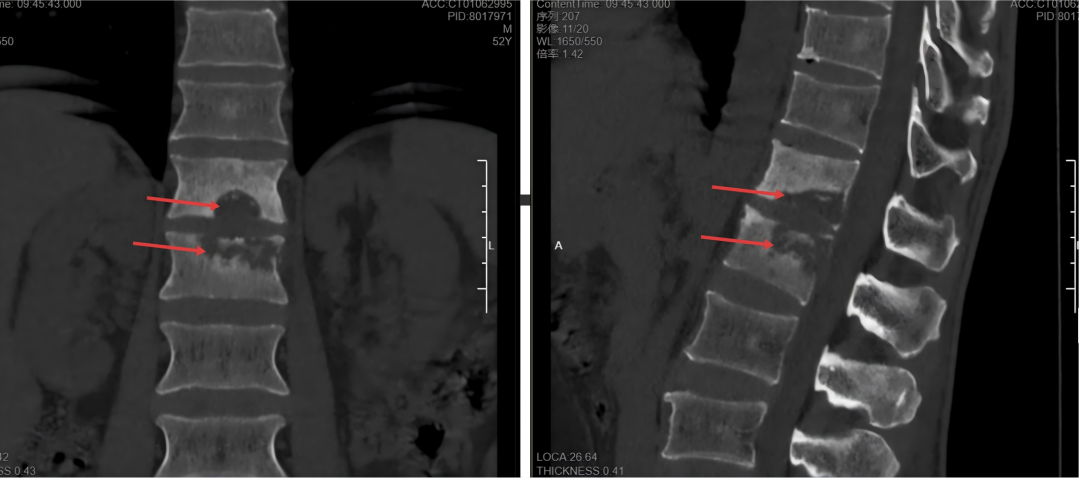

图为部分脊柱结核患者拖延病情后所导致的严重骨质松懈(上图椎体虫蚀样骨松懈)和宏大椎旁脓肿病灶(下图箭头)!经过多学科团队合营,kaiyun sports以上病例均得到直率疗养并病愈。